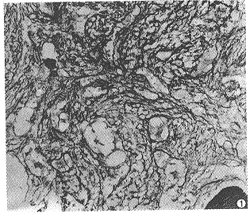

慢性粒細胞白血病慢性期

3.外周血及骨髓原始細胞<5%,可見大量中晚幼粒細胞。